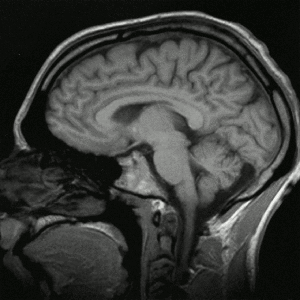

L'imagerie par résonance magnétique (IRM) est une technique d' permettant d'obtenir des vues en deux ou en trois dimensions de l'intérieur du corps de façon non invasive avec une résolution en contraste relativement élevée. L'IRM repose sur le principe de la résonance magnétique nucléaire (RMN) qui utilise les propriétés quantiques des noyaux atomiques pour la spectroscopie en analyse chimique. L'IRM nécessite un champ magnétique puissant et stable produit par un aimant supraconducteur qui crée une magnétisation des tissus par alignement des moments magnétiques de spin. Des champs magnétiques oscillants plus faibles, dits « radiofréquence », sont alors appliqués de façon à légèrement modifier cet alignement et produire un phénomène de précession qui donne lieu à un signal électromagnétique mesurable. La spécificité de l'IRM consiste à localiser précisément dans l'espace l'origine de ce signal RMN en appliquant des champs magnétiques non uniformes, des « gradients », qui vont induire des fréquences de précession légèrement différentes en fonction de la position des atomes dans ces gradients. Sur ce principe qui a valu à ses inventeurs, Paul Lauterbur et Peter Mansfield, le prix Nobel de physiologie ou médecine en 2003, il est alors possible de reconstruire une image en deux dimensions puis en trois dimensions de la composition chimique et donc de la nature des tissus biologiques explorés. En imagerie médicale, l'IRM est principalement dédiée à l'imagerie du système nerveux central (cerveau et moelle épinière), des muscles, du cœur et des tumeurs. Grâce aux différentes séquences, on peut observer les tissus mous avec des contrastes plus élevés qu'avec la tomodensitométrie ; en revanche, l'IRM ne permet pas l'étude des corticales osseuses (tissus « durs ») trop pauvres en hydrogène, ni donc la recherche fine de fractures où seul l'œdème péri-lésionnel pourra être observé. L'appareil IRM est parfois désigné sous le nom de « scanner », ce qui en français prête à confusion avec le tomodensitomètre.